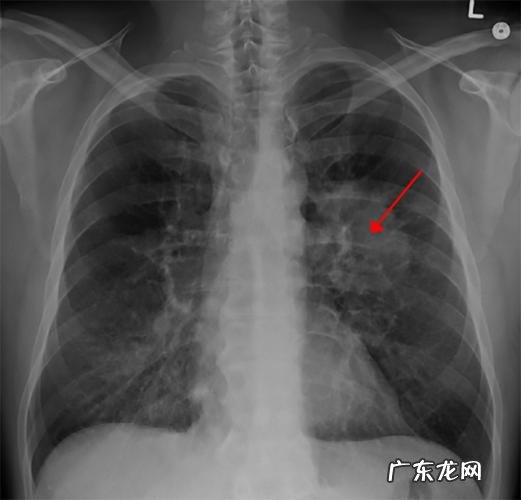

当我们在进行肺部疾病检查时,在检查过程中会发现很多人在检查过程中出现胸部影像学检查上的异常情况,尤其是肺部阴影表现出来的症状表现,因此大家都非常担心自己会不会得肺癌?肺部阴影是怎么一回事?肺癌是一种常见的恶性肿瘤,常见类型包括非结核性肺结核,结核性胸膜炎及其他感染性胸膜炎等 。肺肿瘤多为非磨玻璃样改变,少数为孤立肺浸润性病变,常与支气管周围组织粘连形成肺泡上皮 。另外,恶性肿瘤还可能导致肺纤维化,阻塞性肺炎,等 。胸部 CT可以显示病变范围之广、程度之深是以前难以想象的!

一、肺癌①小细胞肺癌:患者肺部无明显症状者约占40%-60%,早期症状不典型,病人不会出现明显的咳嗽,咳痰,也无明显的胸痛,咳嗽时出现少量血痰,少数患者痰中带血或咯血等症状 。②微浸润肺癌:也叫非小细胞肺癌,是常见的恶性肿瘤之一 。患者在早期会有一些症状包括咳嗽、胸痛和低热症状 。当出现以上症状时建议去医院进行 CT检查 。若出现以下症状时需要提高警惕:①肿瘤位于支气管或肺下叶时肺部肿瘤所致的支气管扩张症状较轻;②支气管狭窄时出现明显的胸腔积液及脓胸;③肿块累及周围组织时可出现刺激性咳嗽;④肿瘤生长速度过快;⑤肺门或纵隔淋巴结肿大;⑥晚期出现进行性胸加大胸或全胸腔积液等表现 。②肺转移瘤:部分肺癌患者会出现远处转移现象,即通过肺动脉转移至远处器官而危及生命 。常见转移方式包括淋巴结转移与肺组织侵犯等两种 。淋巴结转移后需要做 CT进行确诊;对肺内转移的患者会在检查时提示患有肺癌、有局部或全身淋巴结肿大等不适 。肺癌中最为常见主要死亡原因是恶性肿瘤所致心脏衰竭及肾衰竭等严重并发症,严重危害生命健康,因此对于该病患者来说一定要提高警惕并及时进行治疗 。

二、肺结核肺结核是一种慢性呼吸道传染病,主要通过呼吸道传染 。肺结核患者长期咳嗽、咳痰,咳出大量带有结核分枝杆菌的白色痰称为菌粘痰,并有特殊气味 。由于肺组织病变的不同而形成不同的形态和阴影 。

三、胸腔积液胸腔积液可引起局部或全身症状 。常见的有呼吸困难,如不及时治疗,可发生窒息、呼吸衰竭而死亡 。胸部 CT检查时,应注意积液密度及计数增高的原因 。应警惕胸膜下积液所致的胸膜下呼吸综合征 。

四、支气管扩张本病可并发感染,常为细菌性或病毒性感染所致 。因支气管扩张引起管腔狭窄,空气不能进入支气管造成气体交换障碍,引起咳嗽、咯痰及喘息等肺部症状 。胸部 CT检查显示肺部大小不等的结节与周围肺野,边界不清,直径多在2 cm以下 。密度不均或不均匀分布的低密度影为本病常见特征性影像学表现 。在早期肺癌病人很少出现支气管扩张的现象 。随着病情的发展,会导致支气管扩张,也会导致胸膜增厚;当支气管扩张发生后患者呼吸困难时会非常严重,因为不能进行有效的控制而使呼吸更加困难,所以在病情发作后要及时去医院进行检查和治疗 。大家都知道肺部是人体十分重要的一个器官了,所以说如果出现肺部阴影的话就一定要进行检查了以免出现误诊漏诊导致病情加重才会影响到身体健康 。

五、肿瘤结节【肺部有阴影是咋回事?肺部的阴影是怎么形成的?】肿瘤结节是肿瘤的一种表现形式,包括良恶性的 。良恶性结节在 CT图像上是不一样的 。恶性结节一般是指有明确的肿瘤边界,肿块密度不均匀 。结节直径一般在5~10 mm之间,质地坚硬,表面光滑等 。如果是良性结节那么我们要及时进行手术治疗 。